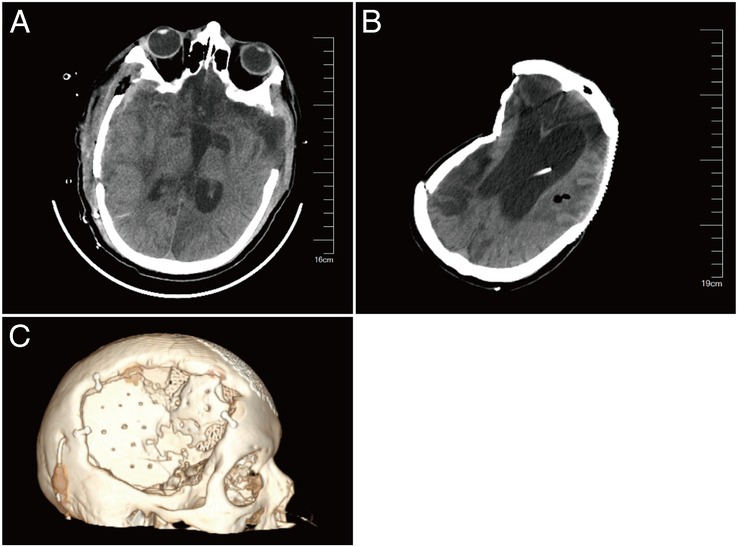

Introduction: Cranial defects, often resulting from decompressive craniectomy, require timely repair to mitigate neurological risks and psychological sequelae. This study compares polyetheretherketone (PEEK) and autologous bone grafts in cranial reconstruction, focusing on clinical outcomes, cost-effectiveness, and utilization trends.

Methods: A retrospective analysis was conducted on the clinical data of 188 patients who underwent skull repair surgery in the neurosurgery department of the First Affiliated Hospital of Shandong First Medical University (Shandong Provincial Qianfoshan Hospital) from June 1, 2015, to August 31, 2022. The patients were divided into a polyetheretherketone (PEEK) group (n=80) and an autogenous bone flap group (n=108) based on the different materials used for skull repair. Analyze the baseline data, repair materials, skull defect duration, hospitalization expenses, surgical information (duration of surgery, presence or absence of blood transfusion), and postoperative complications (epilepsy, hydrocephalus, subdural effusion, bone resorption, and infection) of the 2 groups of patients.

Results: There was no significant difference in baseline data, primary disease, and time of skull defect between the 2 groups of patients ( P >0.05). Comparison showed that traumatic brain injury (54.80%) was the main cause of skull repair surgery, followed by bleeding (22.30%) and cerebral infarction (18.10%). There was no significant difference in hospitalization time between the 2 groups of patients ( P >0.05), and there was no significant difference in the postoperative recovery of skull repair materials. However, the hospitalization cost of the PEEK group was higher than that of the autogenous bone group, and the difference was statistically significant ( P <0.05). The surgery time of PEEK group patients was shorter than that of the autogenous bone group, with PEEK 144 (109-185.75) minutes and autogenous bone 171.5 (155.25-187) minutes, respectively, and the difference was statistically significant ( P <0.05). In terms of postoperative complications, a total of 82 people experienced complications during the 3-month follow-up, including 19 people in the PEEK group (23.70%) and 63 people in the autogenous bone group (58.30%). There was no significant difference between the 2 groups in postoperative epilepsy, hydrocephalus, infection, etc. ( P >0.05). In terms of material selection for repairs, the use of PEEK has been on the rise year by year, and as the number of repair personnel tends to stabilize, the proportion of PEEK usage has been increasing year by year.

Conclusion: PEEK emerges as a cost-effective, clinically robust alternative to autologous bone grafts, particularly for complex defects. Policy interventions, including DRG-exempt payments and volume-based procurement, could further enhance its accessibility. These findings support broader adoption of PEEK in cranial reconstruction, balancing upfront costs with long-term clinical and economic benefits.